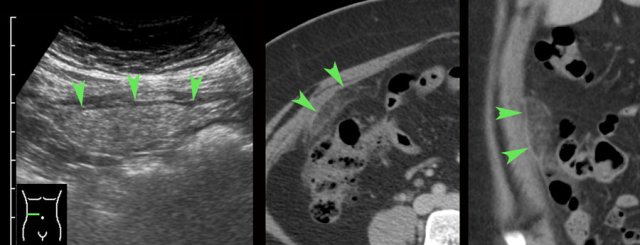

In this patient submitted for suspected stomach perforation, a large inhomogeneous mass of blood clot (arrowheads) in the left peritoneal cavity was visualized (right upper image).

Such a

large clot can easily be mistaken for normal mesenterial fat or bowel.

Awareness

and careful inspection of this mass, which lacks peristaltic movements, are helpful findings to differentiate.

This patient had also a lot of free fluid, which at puncture was liquified blood (right lower image).

Laparoscopy demonstrated 1.5 liter of blood and a ruptured tubal pregnancy.